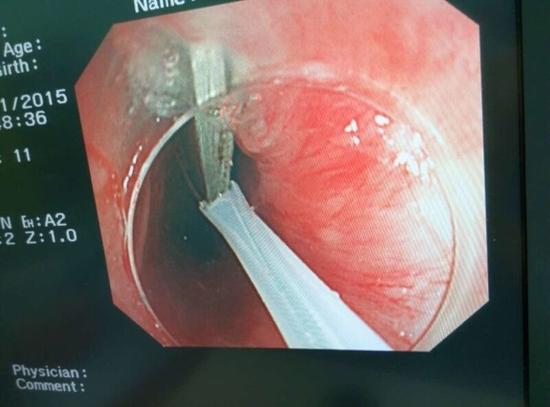

醫(yī)生從華先生胃里取出的鑷子和打火機

隨后,范醫(yī)生先用圈套器套取出了長10厘米的鑷子,再一個一個地取出了打火機。整個取出過程小心謹慎而又一氣呵成,只用了不到10分鐘。